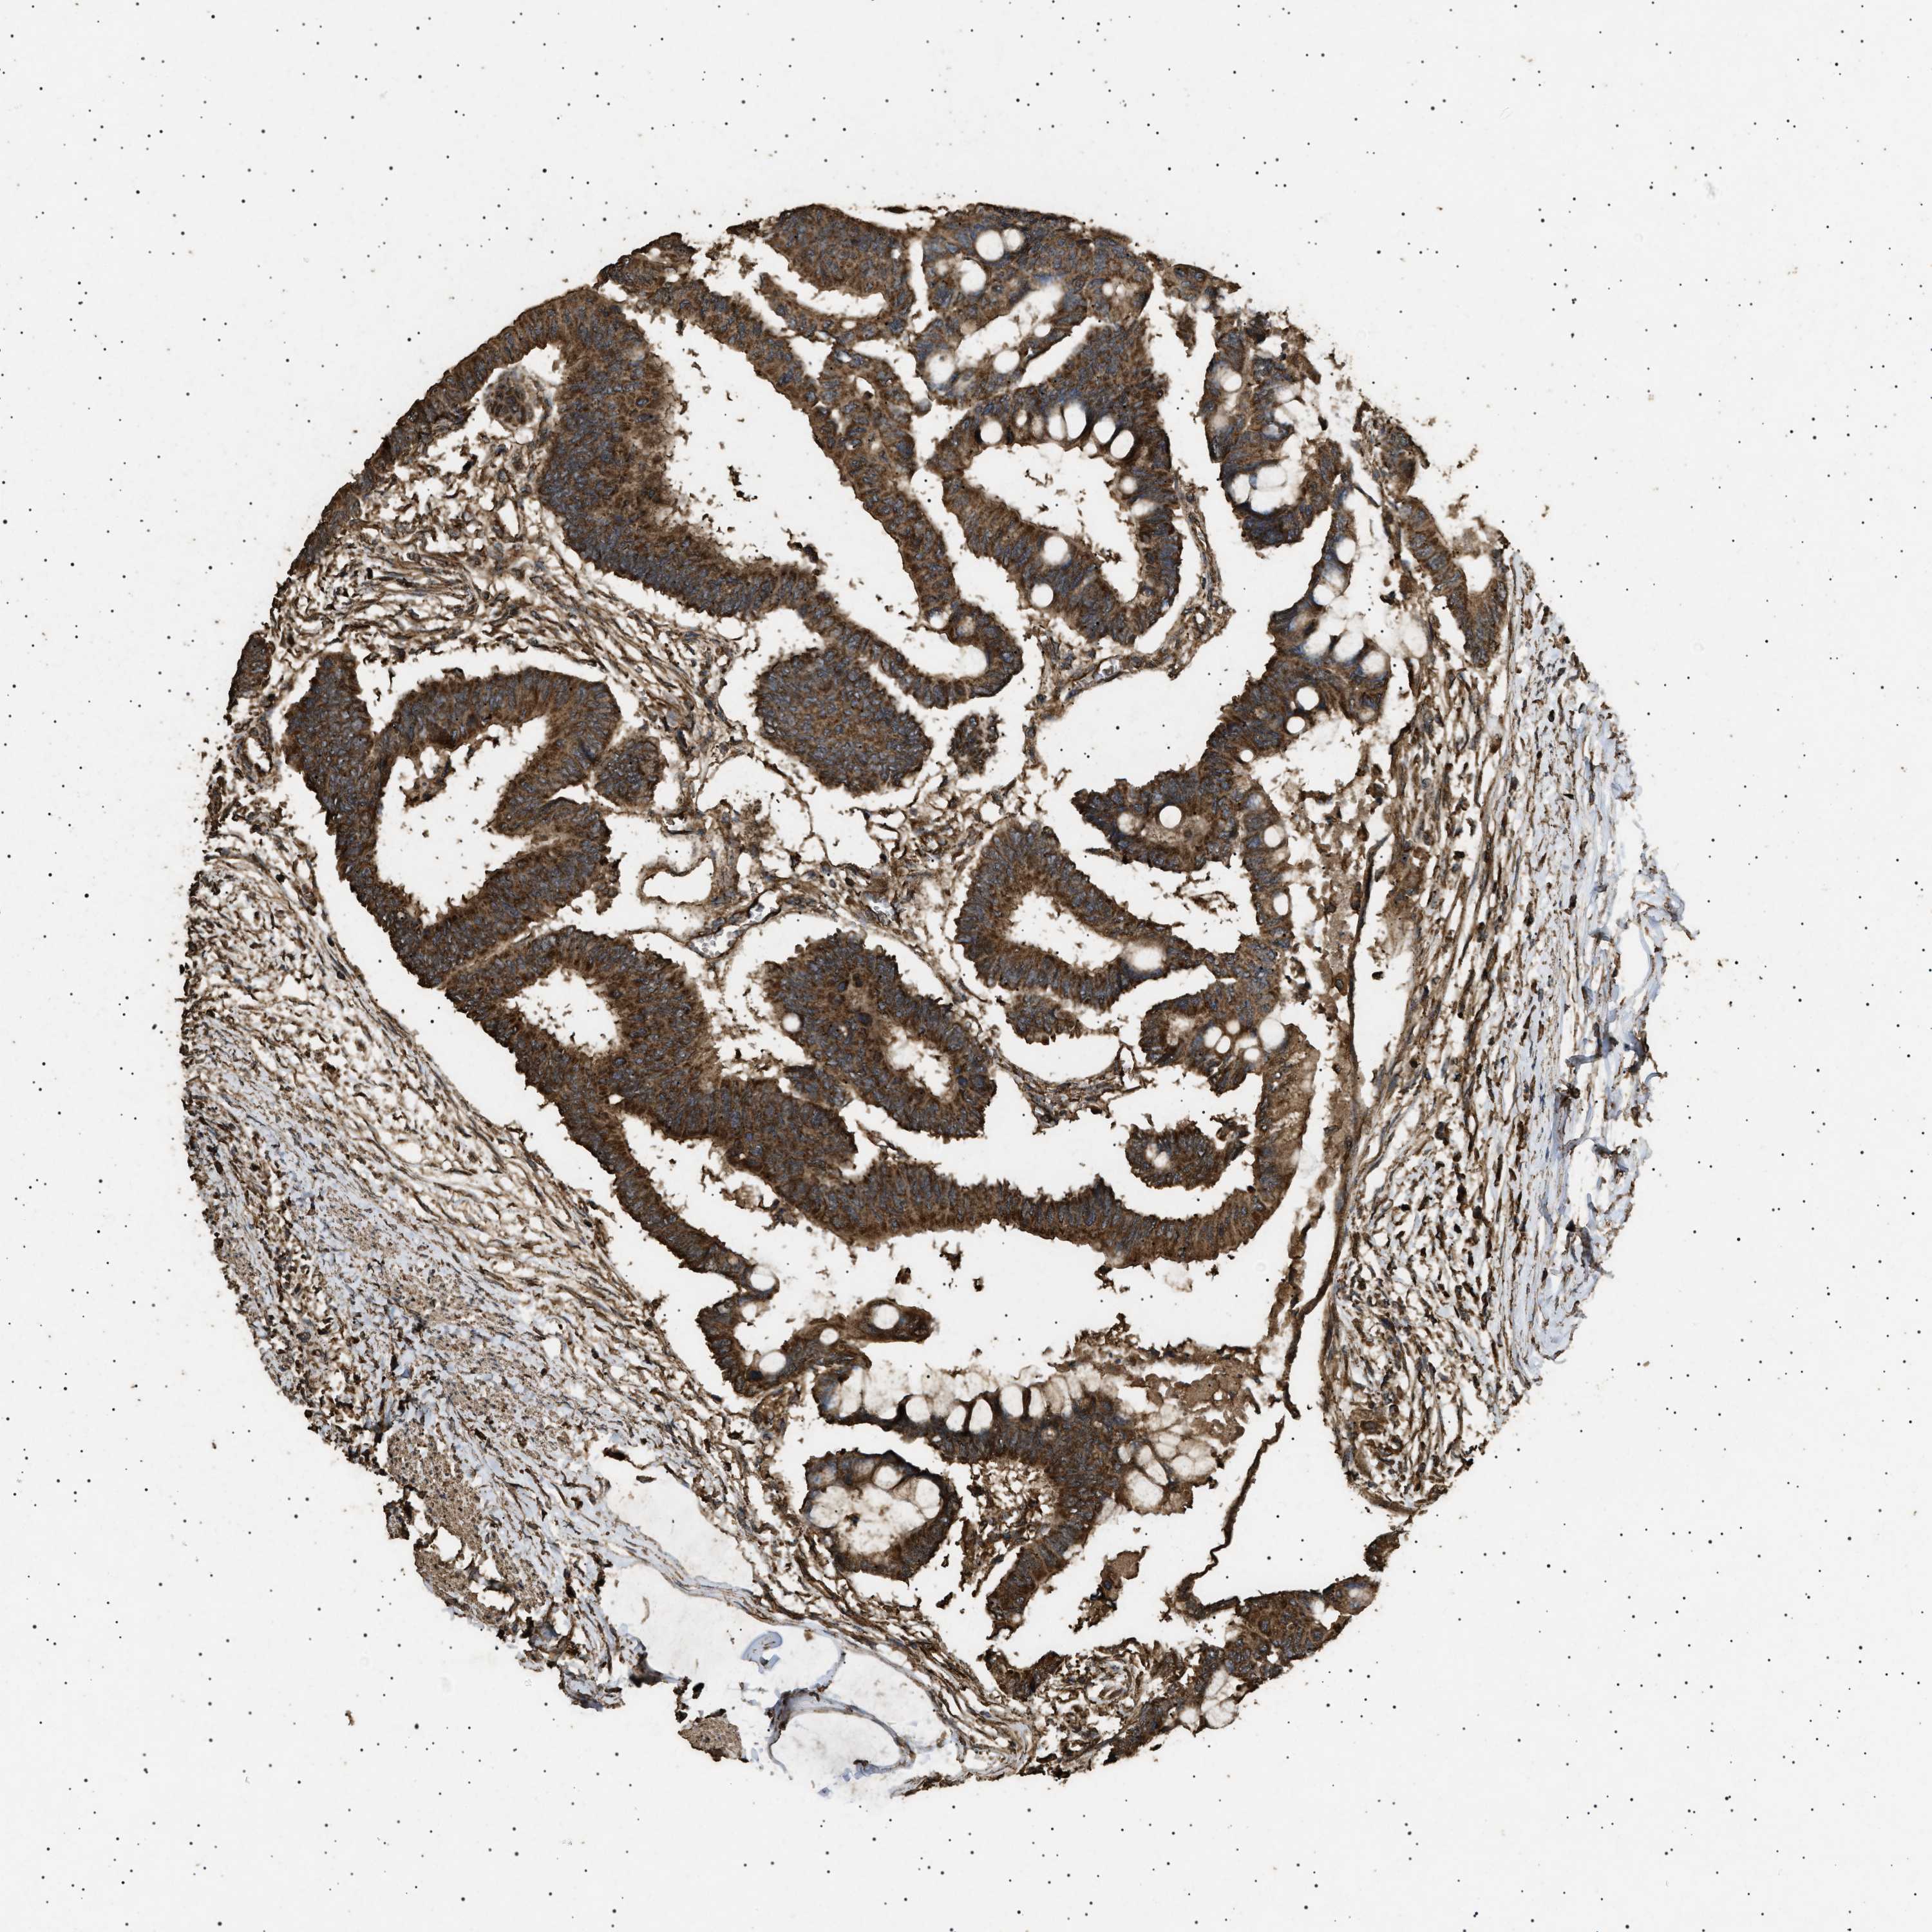

CANCER COLORECTAL CANCER Show tissue menu

Colorectal cancer

Human cancer

Rectum adenocarcinoma